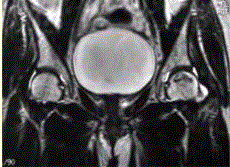

问题 患者男,47岁,左髋部疼痛及压痛6个月,“4”字试验阳性。左髋关节内、外旋活动受限。检查提示:左髋关节活动轻度受限,大腿上部轻压痛。血常规检查正常。髋关节CT及MRI如下图。 对本病例,你首先考虑的诊断是

选项 A.骨髓炎 B.左股骨头缺血性坏死 C.退行性关节病 D.关节结核 E.骨岛 F.左髋关节腔积液

答案 BF